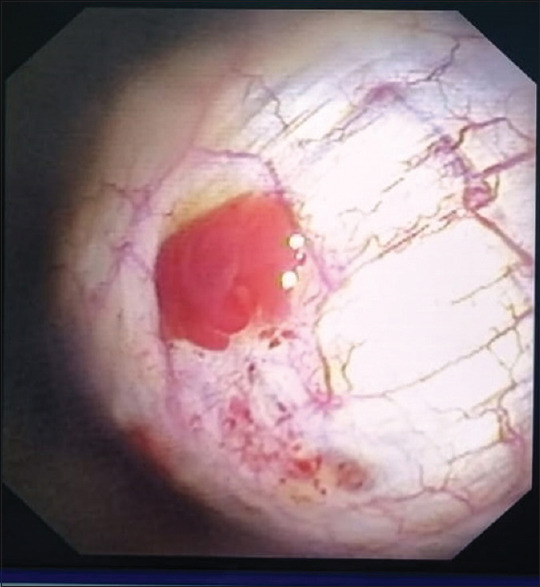

Abstract: Endometriosis is an ectopic implantation of uterine tissue and can affect the thoracic cavity, resulting in Thoracic Endometriosis Syndrome (TES). TES is rare and presents with catamenial pneumothorax, haemothorax, and hemoptysis, often coinciding with menstruation. We report a case of a 46-year-old female with a decade-long history of hemoptysis and periodic chest pain associated with her menstrual cycle. High-resolution CT scans revealed persistent pneumothorax and pleural nodules. A dry thoracoscopy was performed, and biopsies confirmed the diagnosis of TES through histopathology and immunohistochemistry. This case highlights the importance of considering TES in women with cyclic respiratory symptoms and demonstrates the diagnostic value of dry thoracoscopy in benign conditions of the pleura. Raising awareness among clinicians is crucial for timely diagnosis and management of TES, reducing patient morbidity.

Abstract Image